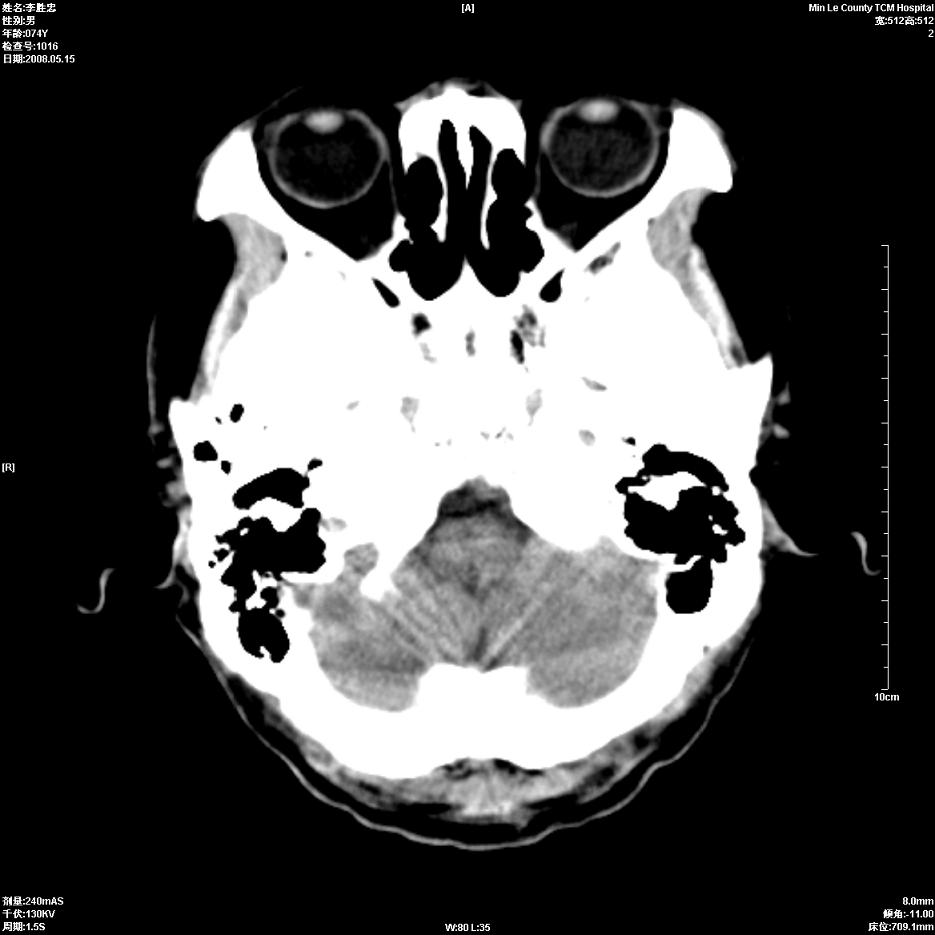

以下是引用hhcckk在2008-5-30 14:26:00的发言:[br]病灶跨中线,有占位效应,强化不明显,考虑胼胝体区低级别的星形细胞瘤可能性大,建议mr检查